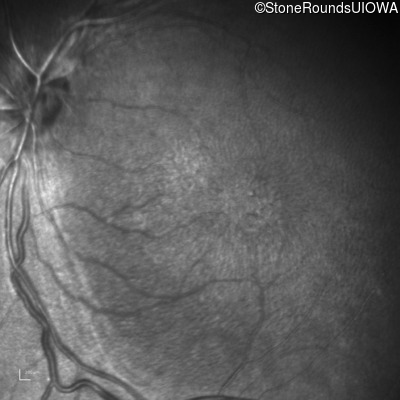

Infrared Fundus Photograph - Right - 20/200

Exemplar

Infrared Fundus Photograph - Left - 20/150